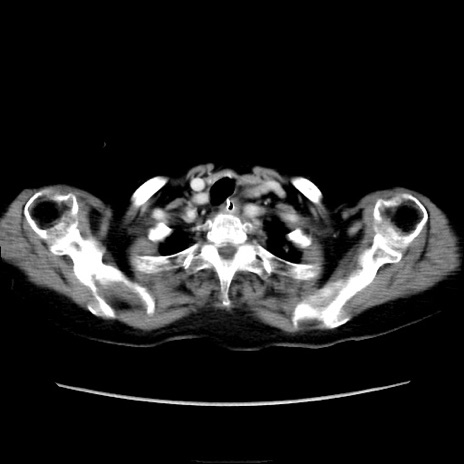

症例40(横断像)

横断像